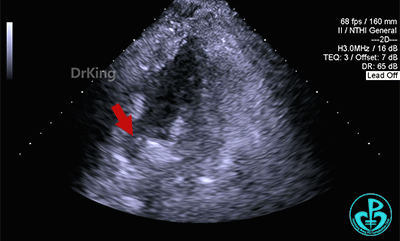

多切面观察封堵器位置形态,封堵器骑跨于缺损左右两侧。

锁定前,四腔心切面显示封堵器形态良好,牵拉试验,封堵器骑跨于缺损两侧,封堵器整体稳定,仅右盘随钢缆牵拉移动。

剑下双房心、四腔心切面观察封堵器,位置正确、形态良好。